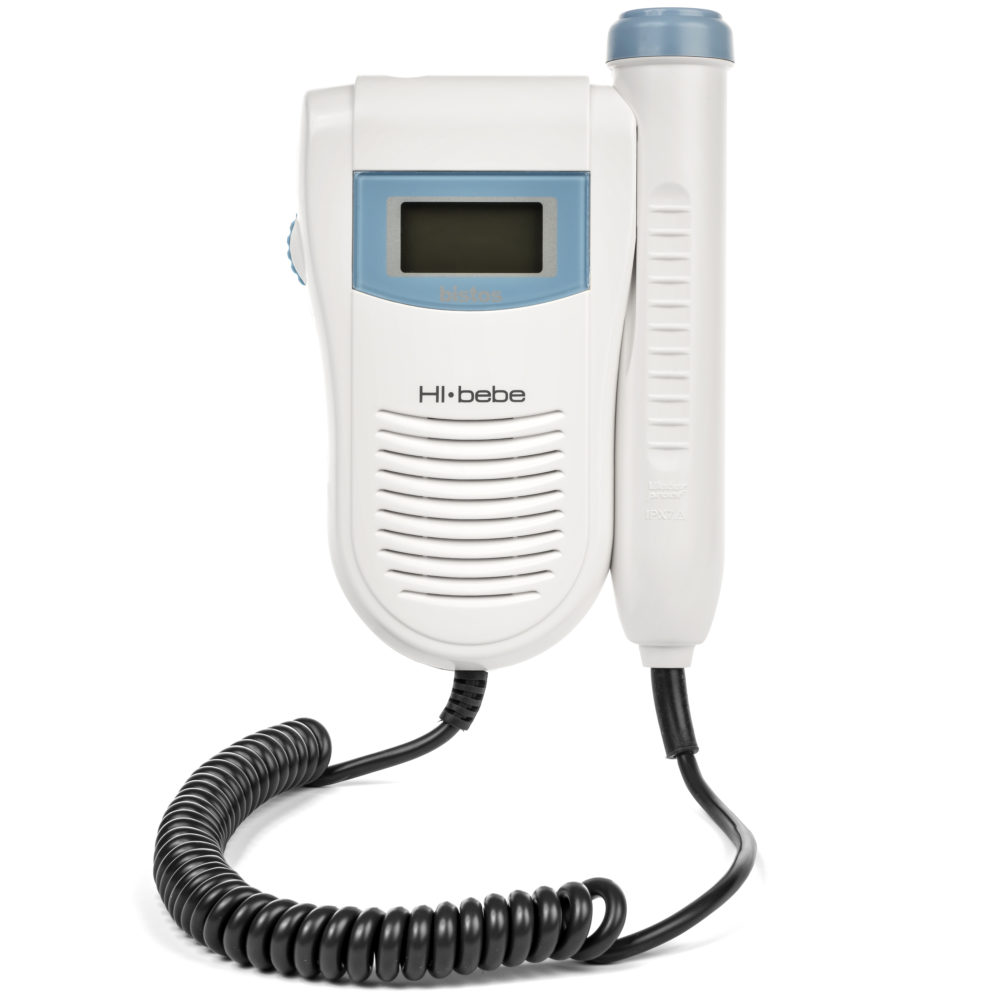

FETAL DOPPLER

FETAL DOPPLER